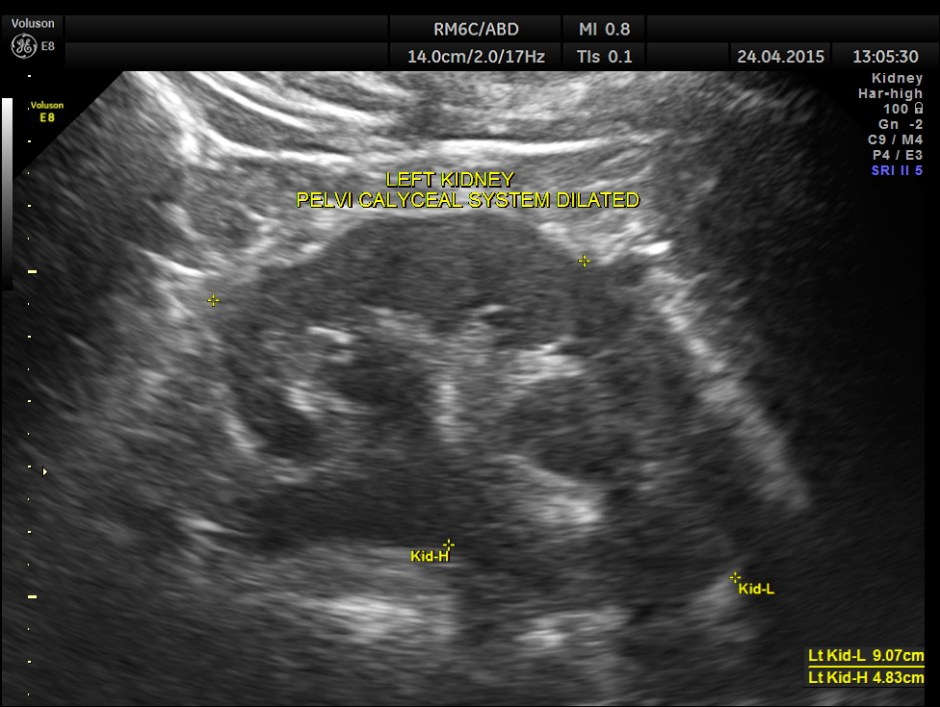

His ultrasound at present showed :

The kidneys show mild pelvi calyceal dilatation.